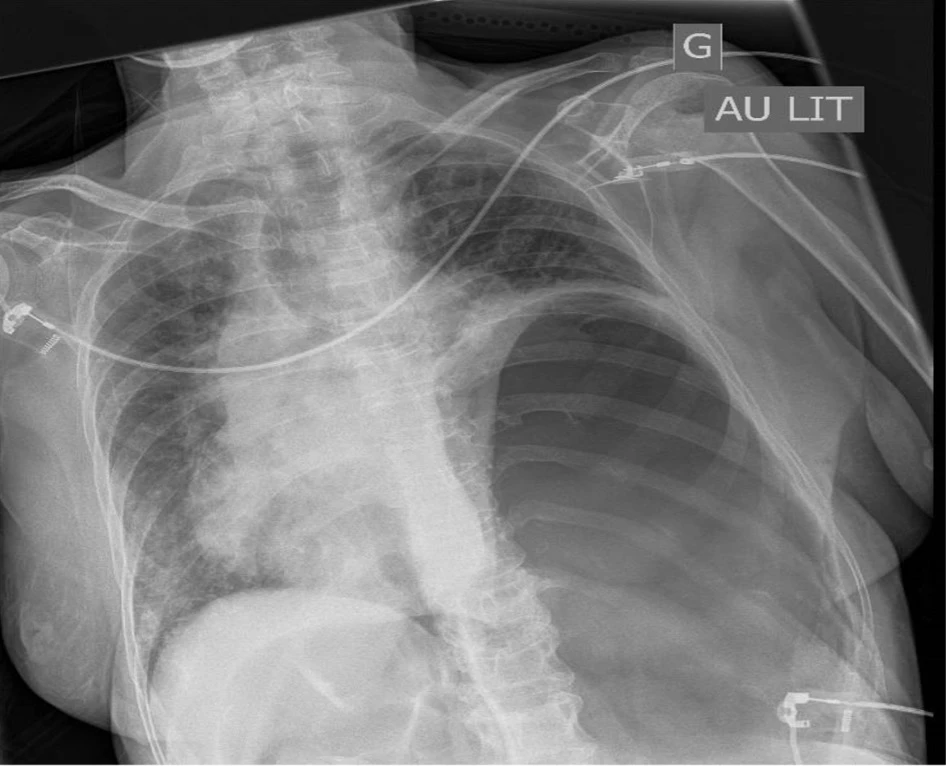

Une patiente, résidente en foyer, présente une toux avec état fébrile depuis quelques jours, avec apparition le jour de son admission d’une dyspnée aiguë avec des troubles de l’état de conscience.

A l’arrivée sur site de l’équipe préhospitalière, ses signes vitaux sont :

- TA 150/90 mmHg

- FC 110/​min

- SatO2 70% AA qui remonte à 85% sous masque O2 haute concentration

- FR à 40/​min avec respiration superficielle.

Elle bénéficie de ventilation assistée au ballon durant son transport au déchoquage. La radiographie de thorax au déchocage est la suivante.

Quel est ton diagnostic ?